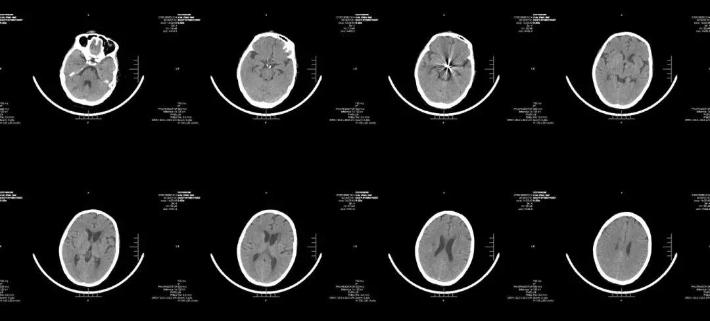

当地医院头颅CT

侧脑室穿刺引流术后复查头颅CT

术后1周复查头颅CT